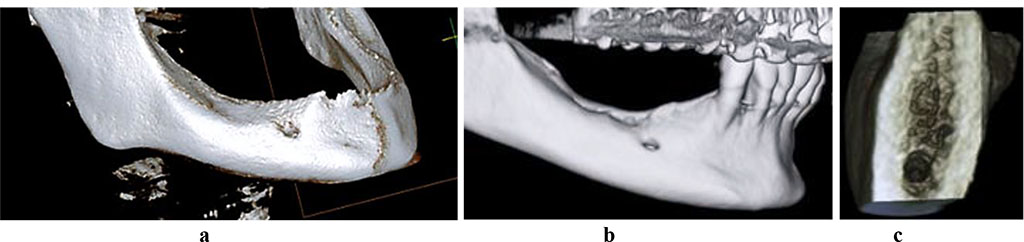

To measure the bone tissue volume in the mandible alveolar part, as well as to study its microarchitectonics, cone-beam computed tomography (CBCT) was performed using a Galileos GAX5 machine (Sirona Dental Systems, Germany). There was also postprocessing of images done involving the construction of panoramic and other multiplanar reconstructions, using the specialized GALILEOS Viewer software. In the basic interface, the studied area was highlighted as the centerline on the panoramic reformat, which was followed with automatic volumetric rendering in a multi-plane format (axial, coronary, sagittal projections, 3D window). The function of selecting the selected layer’s thickness allows segmenting the required area from the entire mass, evaluating the quantitative features of the bone tissue, while in a cross-sectional 3D window it allows detailing microarchitectonics with an evaluation the spongy and cortical bone status (Fig. 2).

Figure 2. 3D-reconstruction of the mandible with a full (a) and a partial (b) adentia, 3D cross-section of the mandible alveolar part, with neither osteoporosis nor osteopenia observed (c).

Of the control group 19 patients, 10 (52.6%) featured bounded dentition defects; 6 males (31.6%) had unilateral free-end space defects; 3 (15.8%) had bilateral free-end space defects. The CBCT data showed out of 19 patients in the control group, 17 patients (89.5%) had a sufficient volume of bone tissue (category A based on the classification by C.E. Mich, K.B.M. Judy (1987)) at the area of missing teeth, whereas another 2 patients (10.5%) had a minimum sufficient volume of bone tissue (category B according to C.E. Mich, K.B.M. Judy (1987). The CT scans in the cross-sectional 3D window of the planned dental implantation zone, showed that the compact bone in the lower jaw was uneven in width (thinned at the top of the alveolar ridge, thickened at the periphery). In the mandible dentition defects, the area of the spongy bone was slightly reduced, the bone trabeculae of the spongy bone were wide and attached tightly to one another, intertrabecular space was basically not observable, the vestibular and lingual cortical plates were to be visualized, while the trabecular package was completely intact (Fig. 4).